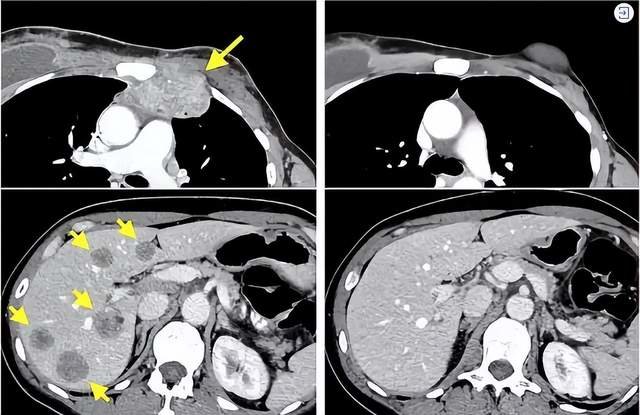

左图黄色箭头是治疗前肿瘤位置;

右图是免疫细胞治疗结束14个月后的复查:肿瘤完全消失